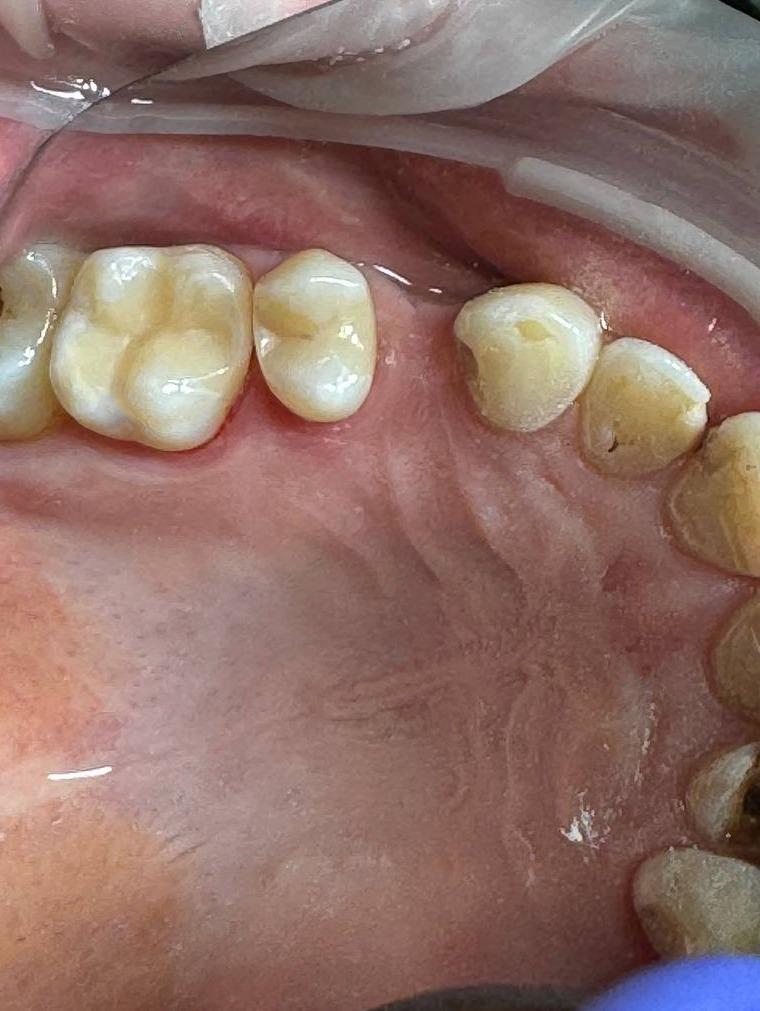

Пациент40 лет, жалобы на боль от термических и химических раздражителелй. Произведено лечение кариеса 14,15 зубов под микроскопом в условиях седации.